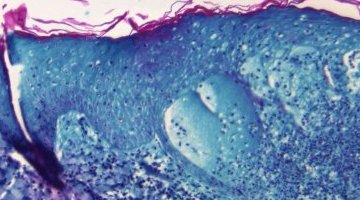

Environ la moitié des cas de choléra détectés à Haïti concernent des enfants, dont beaucoup sont ...

L’épidémie mondiale de choléra a explosé depuis le début de l’année. Avec 31 pays concernés dans ...